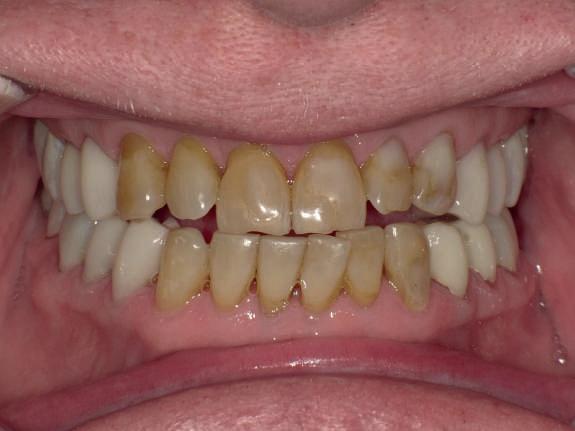

Pe parcursul ședințelor de întreținere parodontală ulterioare, valoarea PRS pentru dintele nr. 16 a fost redus la un scor de 5, un prognostic „bun”, cu o probabilitate de 93% de a-și păstra dinții din punct de vedere parodontal după 15 ani și o probabilitate de 80% de a obține acest lucru după 30 de ani. Scorul de implicare a furcației s-a redus, iar furcația vestibulară a dintelui nr. 16 a devenit improbabilă (scor = 1). Scorul de mobilitate a dintelui nr. 16 a fost redus cu 1 (scor = 1).

inferiori stângi nr. 37 și 38, pe care a decis să îi retrateze prin terapie parodontală asistată de laser. Acest retratament a reușit să elimine simptomele și a condus la stabilitate parodontală (fig. 10-13).

10, 11, 12. Imagini clinice la 4 ani după tratament: lateral dreapta (fig. 10), frontal (fig. 11) și lateral stânga (fig. 12). A existat o reducere semnificativă a PD, BOP și a mobilității.